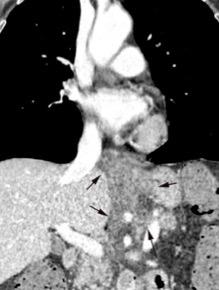

Líneas paraespinales formando un “paréntesis” por encima del diafragma. El signo señala el origen “intratorácico” de la lesión.

Conrad A et al. Pott’s disease associated with large and multiple abscesses in a 30-year-old migrant from Chad. BMJ Case Rep 2018

(lesiones toracoabdominales) La divergencia de las líneas paraespinales apunta a lesión toracoabdominal, que desde el tórax desciende y penetra en el abdomen.

Signo del “iceberg” positivo en Tb vertebral

Afectación por vía hematógena. Región dorsolumbar más frecuente. Afectación inicial: irregularidad de los platillos vertebrales, disminución del disco intervertebral con esclerosis ósea adyacente. Kim. Radiographics.2001